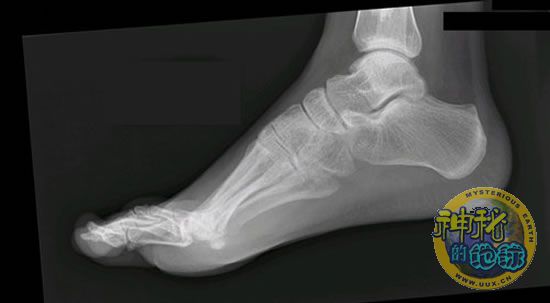

但是,罗利安的研究至少证明了脚趾对跑步的重要性。这项研究刊登在最新一期《实验生物学杂志》上。人在向前走或跑时,一只脚在空中,另一只脚在地面,人体一半到四分之三的重量恰好落在前脚上。罗利安说:“你走步时,一只脚在迈出一步前,另一只脚已经着地。你已经转移了部分身体重量。你的脚趾必须在跑动过程中完成更多的工作,推动你的身体向前。”

实验中,15名志愿者在一个对压力十分敏感的表面上一会儿跑,一会儿走,罗利安的研究小组对他们给这个表面施加的力量进行了分析,结果发现脚趾力量只要增加20%,产生的电动力(motor force)却是原来的两倍。我们可以从更为直观的跷跷板活动来解释这一问题:压力和支点之间的距离可使杠杆力增大。

罗利安还发现,长脚趾在让身体停止活动,或利用它们去引导跑和走所必须的向前倾的活动时,需要耗费更多的体力。这多出来的体力便是由长脚趾耗费的,因此增加了对肌肉的压力和损伤,可能使其成为自然选择的牺牲品。